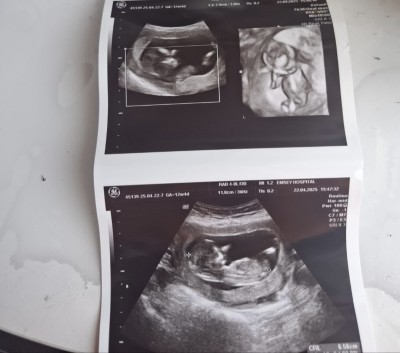

Merhaba kızlar 12 hafta günlük sizce cinsiyeti ne olabilir anlayanlar varmış lütfen banada bakabilrmisiniz

Gebelik haftası 12 haftam4 günlük